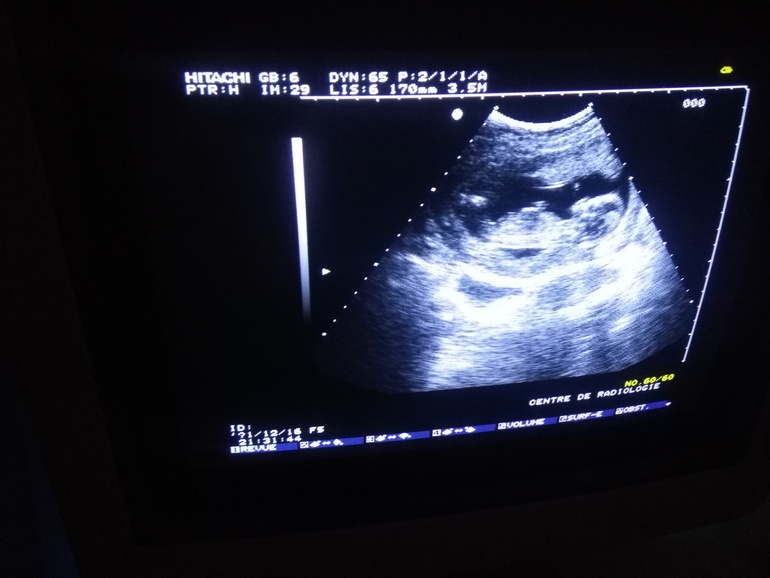

Мне в 17 недель пол сказали...В 21 подтвердили. В 31 неделю было явно видно.